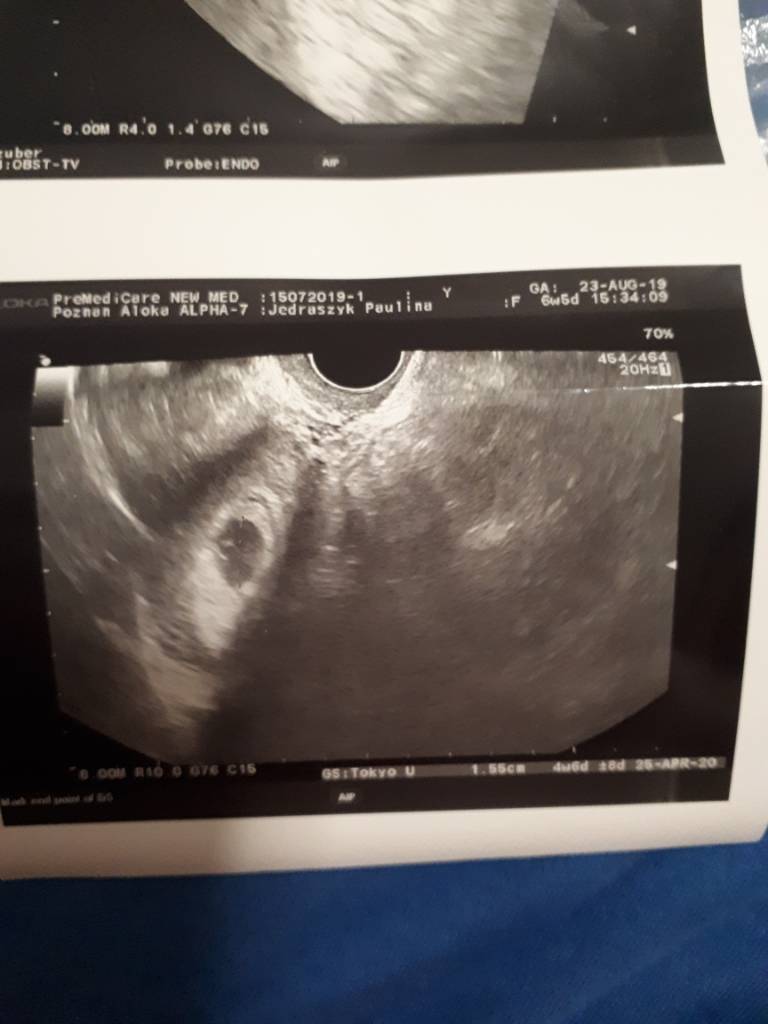

Hej dziewczyny w.obliczeniach wchodzi 6t5d tutaj na usg 5 tydzień co myślicie ? Mam wizytę dopiero za 3 tyg chyba oszaleje . Mówil że Pecherzyk jest

Ciąża młodsza jak u mnie, ile ma pęcherzyk mm?

No właśnie nie wiem napisane jest tylko pod spodem zdjęcia 1.55cm I kompletnie nie rozumiem? Cykle raxzej co 28,30 dni widocznie musiało mi się coś przestawić

Głowy nie dam, ale wydaje mi się że dwa pierwsze zdjęcia to zdjęcia Twoich jajników (lekarz nie robił zdjęć po jednej i drugiej stronie?)

A ostatnie zdjęcie to pecherzyk i widocznie ma 1,5cm. Faktycznie duzy, bo moj w 5+2 mial 8mm, ale inaczej tego zinterpretowac nie umiem